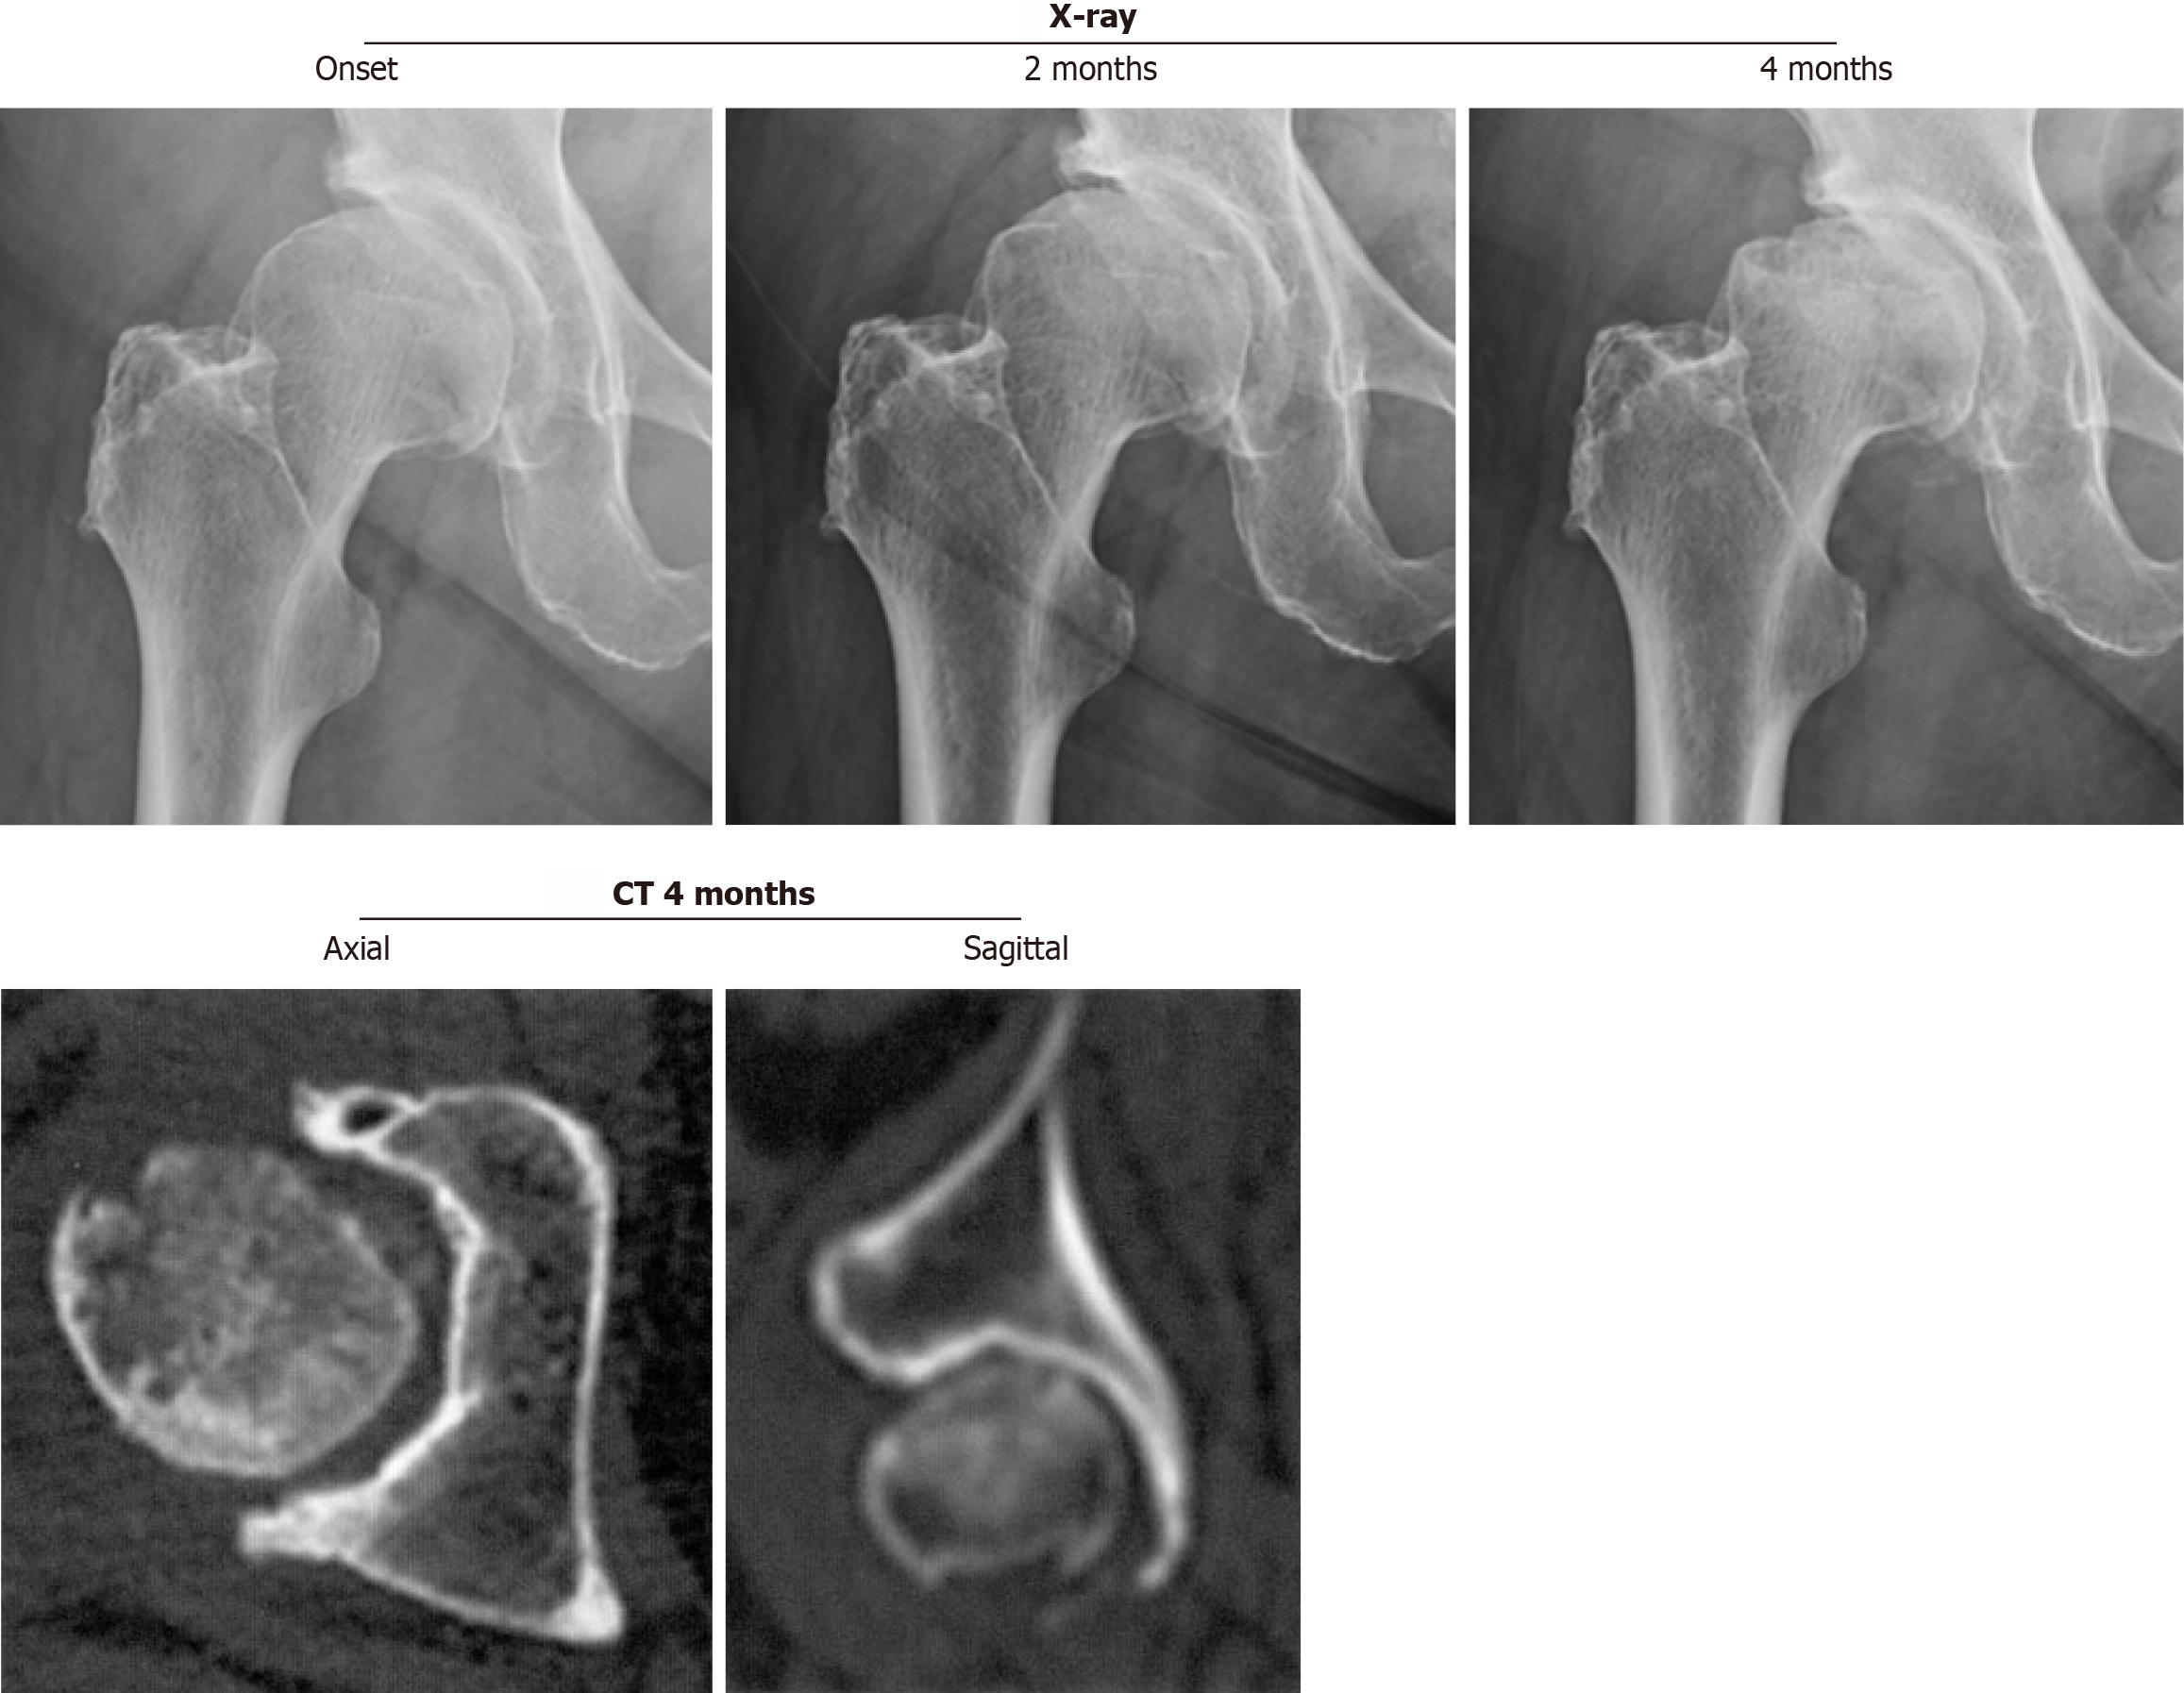

Figure 1 Right hip joint with rapidly progressive osteoarthritis of the hip showing chondrolysis greater than 2 mm/year on a series of radiographs without femoral head destruction on computed tomography at 12 months after the onset.

Magnetic resonance imaging at 6 months after the onset demonstrates inhomogeneous high intensity on the short τ inversion recovery sequence image, including the superolateral portion of the femoral head. CT: Computed tomography; MRI: Magnetic resonance imaging.